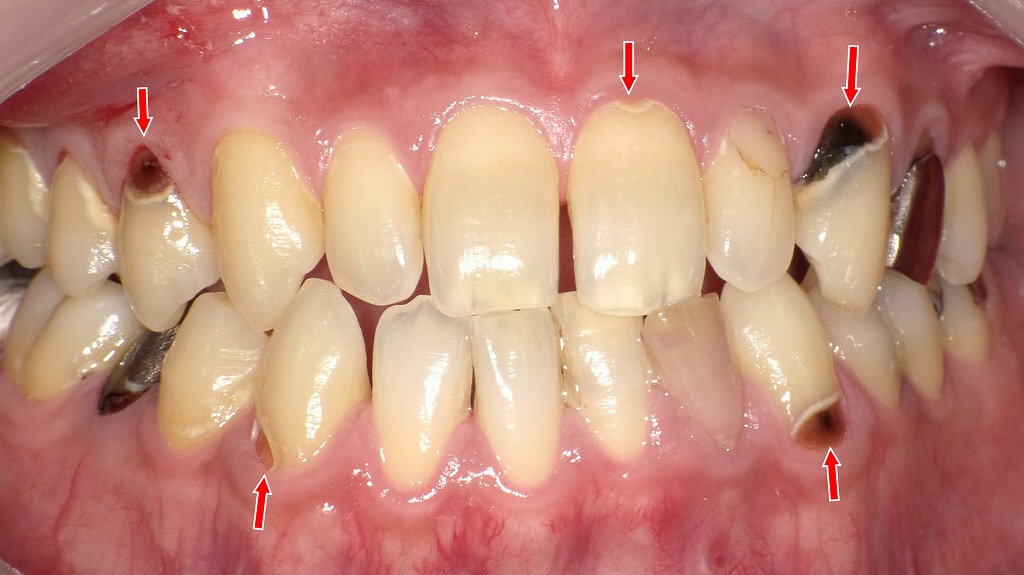

前歯から奥歯まで広がる重度の歯頸部う蝕症例

歯と歯ぐきの境目(歯頚部)に発生した虫歯の症例です。治療前には、歯頚部う蝕や既存のコンポジットレジン充填の変色、二次カリエスが認められました。虫歯を除去した後、コンポジットレジン充填により形態と審美性を回復しています。今回治療した部位以外の虫歯についても、順次コンポジットレジン充填を行い、口腔内全体の健康維持を図っていきます。